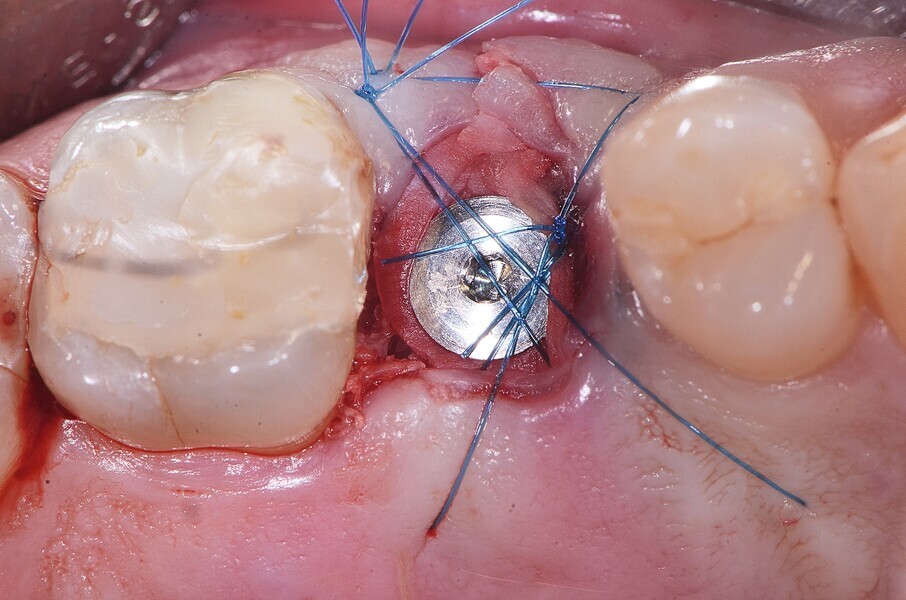

Fig. 20 : Mise en place d’une membrane de collagène et suture.

Fig. 21 : Mise en place d’une membrane de collagène et suture.

Fig. 22 : Mise en place d’une membrane de collagène et suture.

La pose immédiate d’un implant deux pièces en céramique au niveau tissulaire a été accomplie tout en préservant l’alvéole (allogreffe constituée d’un substitut osseux et protection par une membrane de collagène résorbable). La mise en charge n’a pas été réalisée à ce stade (Figs. 12–24)